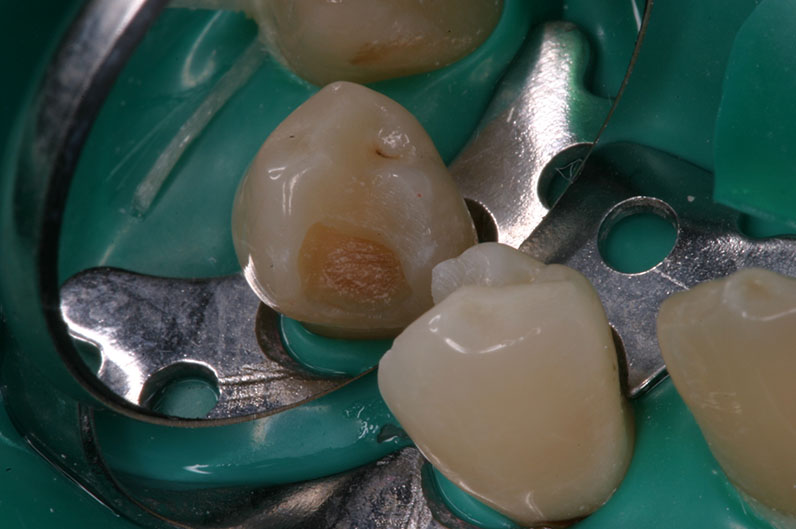

vor Exkavation

mit Proface*

ohne Proface*